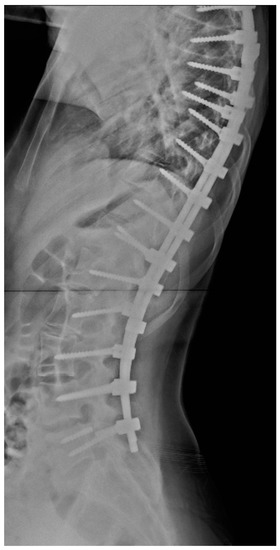

The probability of material failure was 2.73% in the first year after surgery and 10.1% over four years (example, Figure 1). The average time from surgery to diagnosis of the complication was 309 days. Of the 330 patients included in the study, only 21 (6.36%) had implant failure, and of those, only 9 required revision surgery. This fact demonstrates that most patients, even those with mechanical failure, did not need revision surgery due to the absence of clinical complaints or neurological dysfunction.

Figure 1.

Lateral X-ray showing pedicle screw breakage at L5.

The ability to ambulate is a protective factor against material failure (RR, 0.27), and patients with neuromuscular scoliosis, excluding cerebral palsy as an etiology, are 3.33 times more likely to have mechanical failure than patients with idiopathic scoliosis (example, Figure 2). This fact agrees with previous findings in the literature, in which patients with neuromuscular scoliosis or who do not ambulate have higher rates of complications than those with idiopathic or congenital scoliosis [21,22,23]. Possible explanations for this fact are greater curve severity, poorer bone quality and nutrition, lower muscle mass, less subcutaneous and skin coverage, and more unfavorable clinical aspects, such as poor ventilatory function and recurrent infections, among other factors [24].

Figure 2.

Anteroposterior X-ray showing rod breakage on the right.